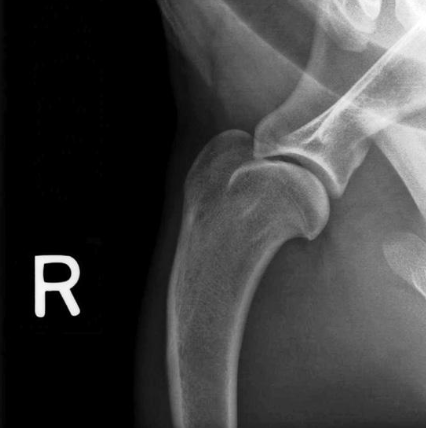

what radiograph view of the shoulder joint is shown?

lateral view